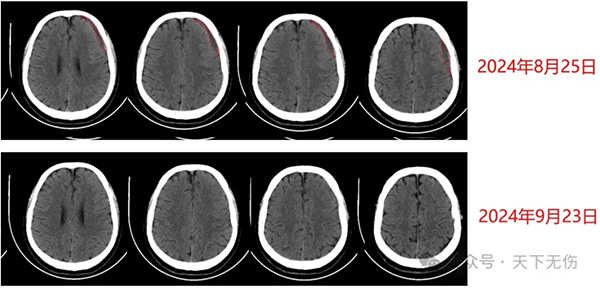

2024年7月15日,他在一位北京著名神经外科教授推荐下从南方来找我,多年的经验告诉我,他的头晕应该就是这个残余血肿引起。然后给予他汀加激素加头颈淋巴按摩疗法,治疗1周出院时复查即已经见到血肿缩小,但头晕减轻并不明显。也因此他仍然忧心忡忡,问我自己到底能否治愈?我反复安慰他,一定会治愈。在接下来漫长的等待药物发挥作用时间中,他间断联系我,说脸上起疹子了,体重增加了,头晕减轻,却仍然没有消失。我感知到他的忧郁,鼓励他,血肿变得越来越小,症状越来越轻,而这些副作用是我们预知的药物副作用,一定会随着停药而完全消失,他的信心逐步增强。9月23日,他突然主动联系我告诉我好消息,说当地医生复查时已经告诉他,他的血肿完全消失了(图2),他的头晕症状也完全消失了。

图2